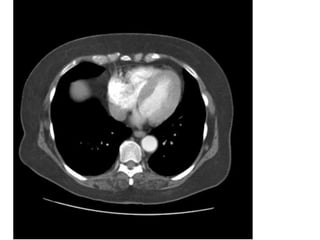

HÌNH 8

1, Right lung. 2, Superior vena cava. 3, Thoracic ascending

aorta. 4, Thoracic descending aorta. 5, Rib. 6, Left Lung.

7, Oesophagus. 8, Trachea.

October 31, 2014 19